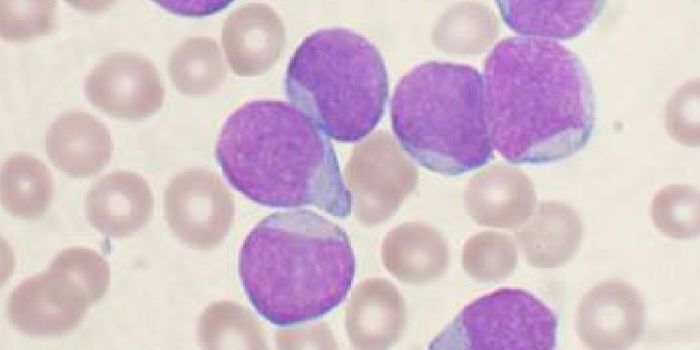

AUG 16, 2017CancerA protein from the “shaggy ink cap” mushroom may be a lethal fighter against leukemia cells, scientists repo ...

AUG 31, 2017CancerFor patients battling leukemia, there is hope in the form of a newly approved gene therapy. Called Kymriah, this is the ...

DEC 20, 2016CancerFor the first time, researchers have traced a childhood form of blood cancer (acute lymphoblastic leukemia or ALL) to a ...

MAR 25, 2024CancerAcute myeloid leukemia (AML), a cancer that develops in the bone marrow and blood when immature white blood cells called ...